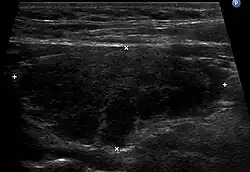

Ultrasound

An ultrasound may be useful in detecting Hashimoto thyroiditis, especially in those with seronegative thyroiditis,[13] or when patients have normal laboratory values but symptoms of autoimmune thyroiditis.[47] Key features detected in the ultrasound of a person with Hashimoto's thyroiditis include "echogenicity, heterogeneity, hypervascularity, and presence of small cysts."[13] Images obtained with ultrasound can evaluate the size of the thyroid, reveal the presence of nodules, or provide clues to the diagnosis of other thyroid conditions.[47]